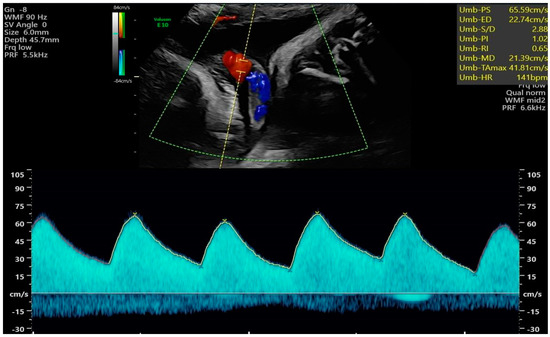

| UMB PI | umbilical artery pulsatility index |

| EDV | end-diastolic velocity |

| PI | pulsatility index |

| RI | resistance index |

| UMBA PSV [cm/s] | 44.17 | 10.09 | 38.90 | 8.10 | –2.99 | 0.004 | –8.77 | –1.77 | 0.59 |

| UMBA PI | 1.15 | 0.31 | 1.09 | 0.25 | –1.03 | 0.305 | –0.16 | 0.05 | 0.20 |